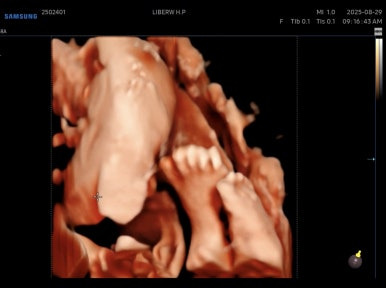

같이 찍어주신 사탕이 손이랑 발

길쭉길쭉한게 이뻤다..^^

그리고 드디어 몸무게도 1kg 넘었다